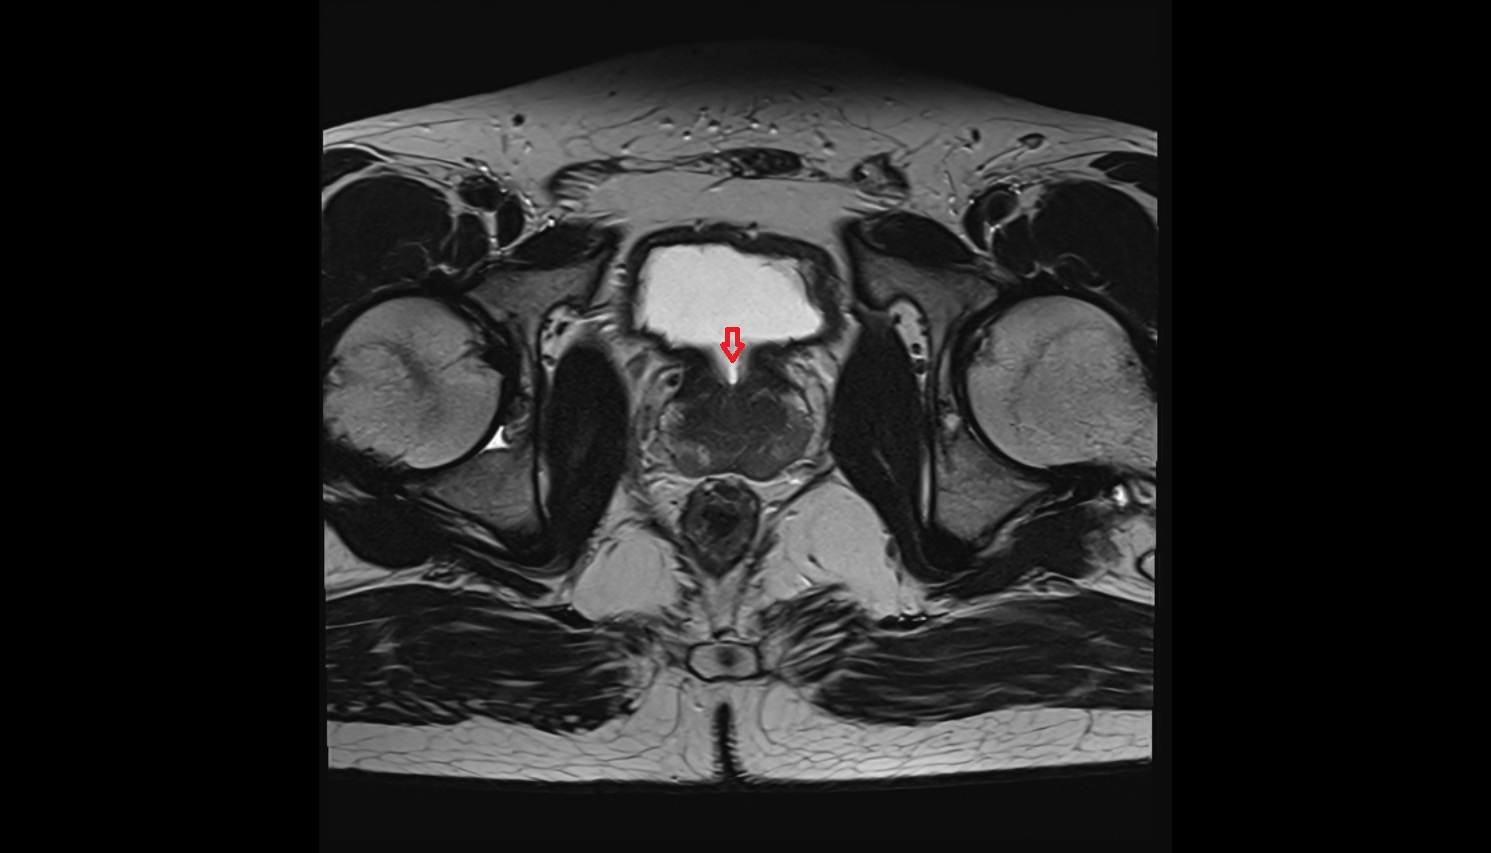

- Uterus

- Body of uterus

- Fundus of uterus

- Cervix of uterus

- Urinary bladder

- Rectum

- Pubic symphysis